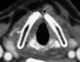

Laryngectomy is the removal of the larynx and separation of the airway from the mouth, nose and esophagus. In a total laryngectomy, the entire larynx is removed (including the vocal folds, hyoid bone, epiglottis, thyroid and cricoid cartilage and a few tracheal cartilage rings). [Source: Wikipedia ]